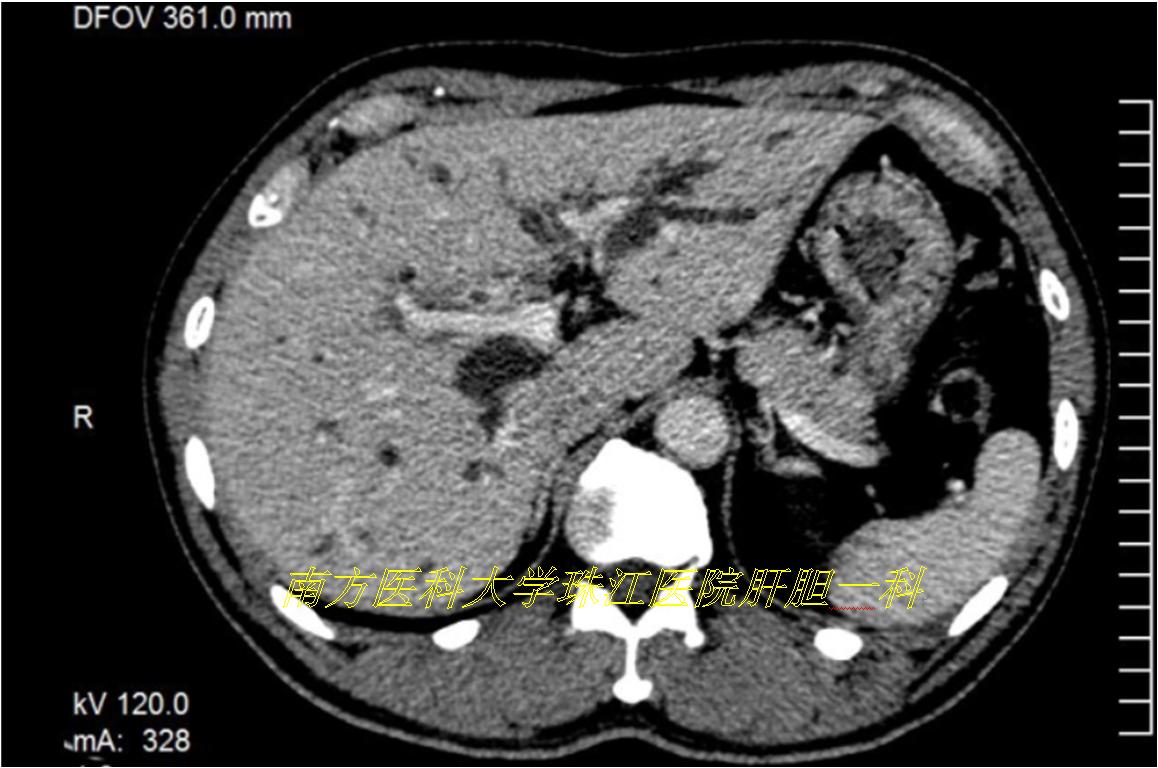

慕名前往,完成老李的三维可视化模型,发现肝动脉及门静脉均存在变异,如果术前未发现这两处变异,贸然进行手术很可能出现相关的并发症。

在三维可视化指导下,方驰华教授团队“顺藤摸瓜”成功地为老李进行肝门部胆管癌根治性切除术,术中情况跟术前三维重建模型完全一致。术后顺利康复出院。